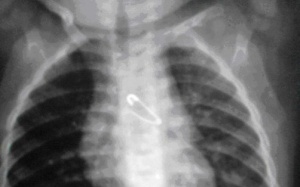

Ngày 12/9, bác sĩ Hoàng Lê Phúc - trưởng khoa tiêu hóa bệnh viện Nhi Đồng 1, TP.HCM - cho biết đã lấy ra được cây kim băng dài gần 2 cm trong bụng bé Bùi Nguyễn Khánh Trinh (6 tháng tuổi, ngụ Kiên...